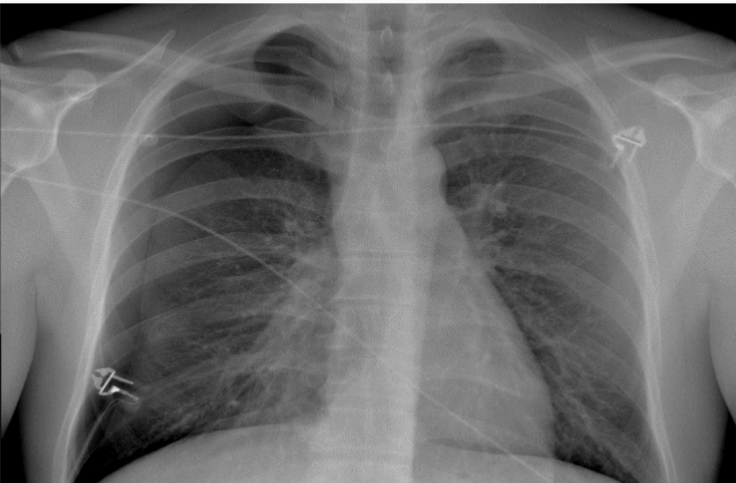

What is this patient presenting with?

Pulmonary edema—classically “Batwing” in appearance

(starts central, spreads outwards)